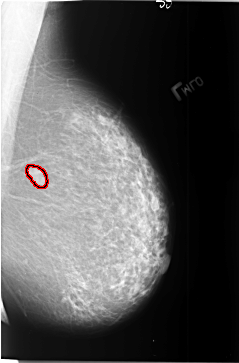

FILE: B_3405_1.LEFT_MLO.OVERLAY

TOTAL_ABNORMALITIES 1

ABNORMALITY 1

LESION_TYPE MASS SHAPE LOBULATED-OVAL MARGINS CIRCUMSCRIBED

ASSESSMENT 4

SUBTLETY 5

PATHOLOGY BENIGN

TOTAL_OUTLINES 1

BOUNDARY